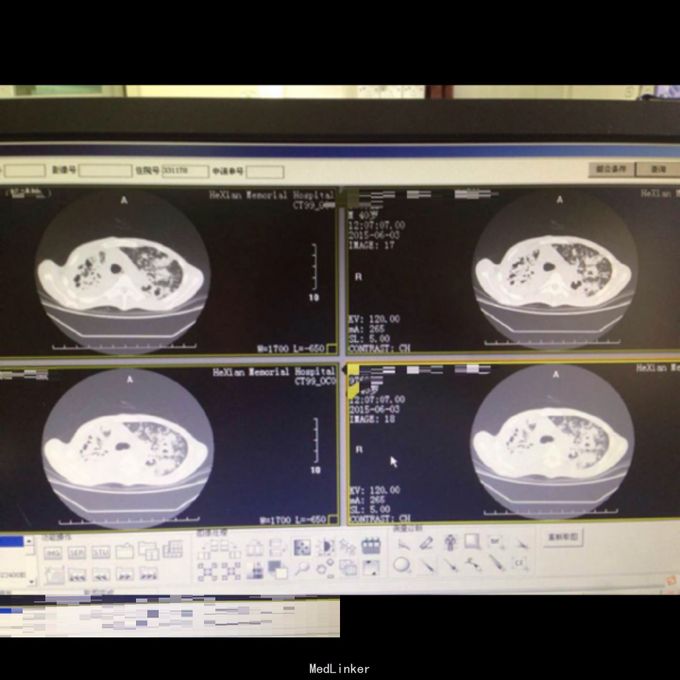

体查:T:36.9℃ R: 23次/分 P:86次/分 BP:130/70mmHg,消瘦,自主体位,神志清楚,对答切题,查体合作。皮肤粘膜未见苍白、黄染,未见皮疹,无皮下出血点,无伤口。全身浅表淋巴结未扪及肿大。口唇红润,伸舌居中,咽部无充血,扁桃体无肿大。颈软,无抵抗,颈静脉无充盈,肝颈静脉回流征(-),气管居中,胸廓对称无畸形、无局部膨隆或凹陷。呼吸平稳,节律规则。双侧呼吸动度对称。双肺部叩诊清音。双肺呼吸音清,双肺未闻及干湿性啰音。心界不大,心率86次/分,律齐,各瓣膜区未闻及病理性杂音。 辅助检查: 双肺CT:1、双肺弥漫性病变,考虑继发型结核,并双肺上叶、下叶背段多发空洞形成、支气管扩张,建议治疗后复查。2、双侧胸膜增厚、粘连,右侧少量胸腔积液。